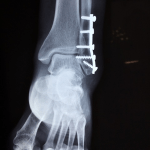

Fracturas por estrés o también llamada fractura por fatiga

Las fracturas por estrés están relacionadas con las pequeñas rótulas de hueso. Se originan por la aplicación constante de fuerza como consecuencia de una...